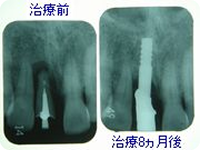

治療前

前歯が歯周病のためグラグラで今にも抜けてしまいそうな状態です。

治療後

抜歯と同時にインプラントを植立し、3ヵ月後にセラミックの冠を装着しました。

治療前と治療8ヵ月後のレントゲン写真です。

手術時に足した人工骨も安定しています。